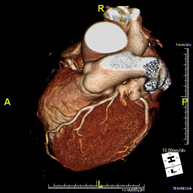

L'angio TC Cardíac o Coronariografia no invasiva és una prova diagnòstica que consisteix en l'estudi de les artèries del cor o artèries coronàries mitjançant l'ús d'un equip TC Multidetector d'última generació i de contrast iodat, i l'obtenció d'imatges bi i tridimensionals. El TC Multidetector o TCMD permet una adquisició d'imatges tan ràpida que es poden valorar les artèries coronàries amb alta precisió anatòmica: estrenyiment o estenosi, calcificacions, variants anatòmiques, etc. ja que gràcies a la seva rapidesa evita l'artefacte que provoca el moviment constant del cor (triga menys de deu segons en adquirir unes 1000 imatges). La informació obtinguda precisa un tractament en estacions de treball amb programes especialitzats en la reconstrucció de les artèries coronàries que permeten valorar el nombre, la localització i les característiques de lesions. Tota aquesta informació s'obté de manera no invasiva: només es requereix la punció d'una vena perifèrica (en el braç). És necessari que la freqüència cardíaca no superi els 75 batecs per minut per això alguns pacients hauran de realitzar un tractament previ amb un fàrmac betabloquejant. - PAAF (punció) de tòrax guiada per TC

- Coronary CT angiography

The Coronary CT angiography or non-invasive Coronarography is a diagnostic test to examine arteries of the heart, or coronary arteries, using state-of-the-art MDCT equipment (64 slices or rows of detectors) and an iodinated contrast agent to obtain two- and three-dimensional images. 64-slice multidetector computed tomography (MDCT) entails high-speed imaging that is beneficial in assessing coronary arteries with high anatomical precision, particularly in evaluating narrowing or stenosis, calcifications, anatomical variants, etc., as its speed prevents the artefact caused by the constant movement of the heart (1,000 images can be obtained in less than 10 seconds). The information obtained requires processing at workstations equipped with specialised software capable of reconstructing the coronary arteries, thereby enabling an assessment to be made of the number, location and characteristics of the lesions. All this information is obtained non-invasively, involving a simple puncture of a peripheral vein (in the arm). To ensure the heart rate stays below 75 bpm, some patients will need preliminary treatment with beta blockers.